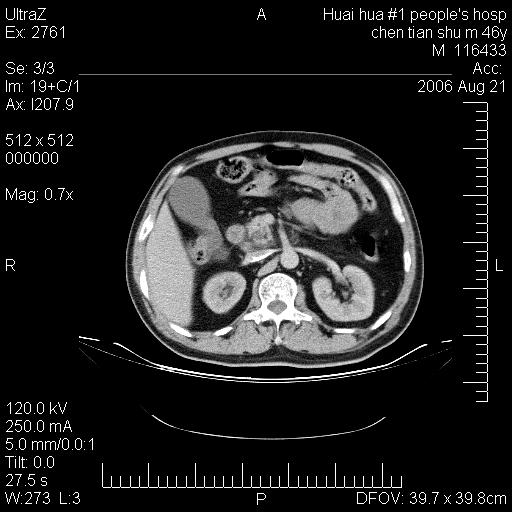

患者,男,46y。腹痛2月,消瘦。

手术病理结果:原发性小肠恶性淋巴瘤(primary gastrointestinal lymphoma,pgil)是原发于胃肠的淋巴网织系统的恶性肿瘤,在结外淋巴瘤中居第一位,该病少见,临床无特异性,诊断困难,术前主要依靠影像学诊断。胃肠道本身具有较丰富的淋巴组织,因而胃肠原发性淋巴瘤是结外淋巴瘤最常见的部位,文献报道约占胃肠道恶性肿瘤的1%~4%,其中胃约占50%~70%,小肠约占35%~70%,结肠约占4%~6%。影像检查在pgil的诊断及分期中有重要的作用,ct是很有价值的检查方法。

胃肠淋巴瘤病理特点:胃肠道原发性淋巴瘤起源于胃肠壁固有层和黏膜下层的淋巴组织即胃肠粘膜相关淋巴组织(malt),多为粘膜相关淋巴瘤。病理上通常为非霍奇金淋巴瘤,且决大多数来源于b淋巴细胞,很少见于霍奇金淋巴瘤。胃肠原发淋巴瘤比胃肠道癌的发病率要低的多,最常见于胃,其病因可能跟幽门螺杆菌感染有关。幽门螺杆菌能引起胃粘膜损害,引起炎性及免疫反应,淋巴细胞聚集并形成滤泡,可影响胃的正常生理功能,导致胃淋巴瘤的发生。单纯性小肠淋巴瘤是常见好发于回盲末端,受累的肠段较长,可单发、多发,甚至累及整个小肠。原发性大肠淋巴瘤罕见,以直肠和盲肠最多见。病变大体观可表现为胃肠腔内外的肿块,也可表现为从黏膜下到浆膜面肠壁的纵向浸润,并且常常伴有肠系膜淋巴结肿大。任何情况下,肿瘤几乎总是导致一定程度的肠壁增厚,可对称或不对称,病变与正常组织间常无明确分界,肠腔可狭窄、正常或动脉瘤样扩张,后者主要是肿瘤在肠壁内浸润,破坏肠壁内植物神经丛所致。以上改变成为ct检测病变的病理基础。

肠道淋巴瘤的ct表现分为4类

1) 壁内浸润型, (2)多发结节型, (3)肠系膜受累伴腔外肿块型(本型就是),(4)肿块型。